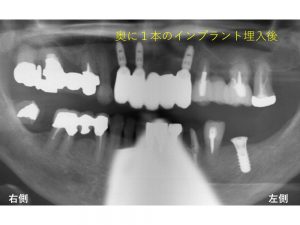

以下が実際にインプラントを1本埋入した後のレントゲンです。

この後インプラントが骨とくっつくまで約2ヶ月待ちます。